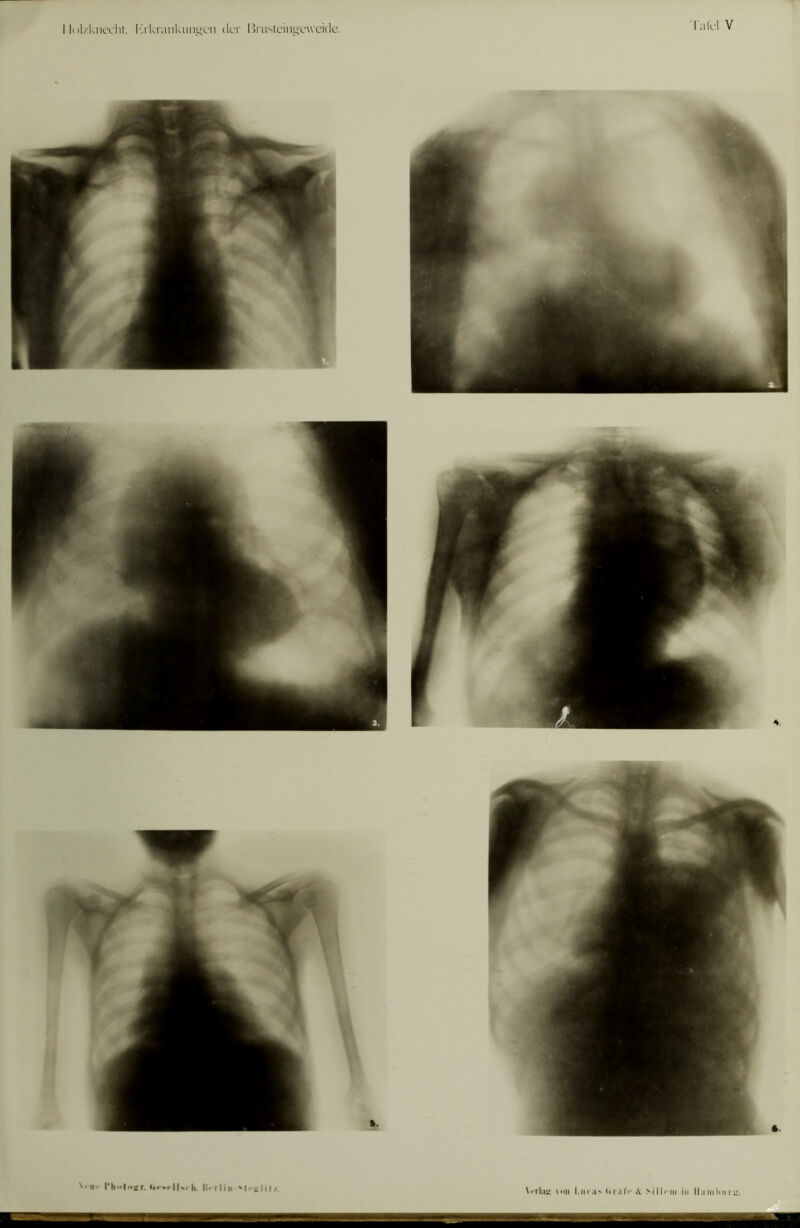

Die röntgenologische Diagnostik der Erkrankungen der Brusteingeweide : mit 60 Abbildungen im Text und 50 Röntgenbildern auf 8 Tafeln.

- Guido Holzknecht

- 1901